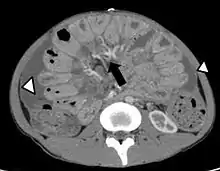

Carcinomatose péritonéale : examen illustré des résultats de la tomodensitométrie ou scanographie.

• échographie, scanner : non indiqués pour le diagnostic des péritonites, peuvent cependant apporter des renseignements quant à leur cause[6].